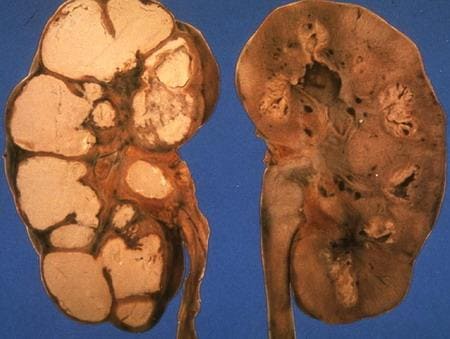

Почка при туберкулезе

Оперативное лечение туберкулеза мочеполовой системы носит радикальный характер. К примеру, при третьей или четвертой стадии нефротуберкулеза больные нуждаются в удалении всей почки. Правда, в туберкулезной хирургии есть правило, согласно которому скальпель не должен распространять по ране микобактерию. Именно поэтому, операция проводится в «холодный» период заболевания, после годичного курса антибактериальной терапии.